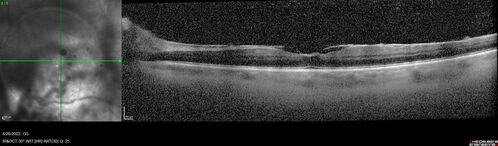

Recurrent toxoplasmosis

63 year old female with history of floaters and vision loss in the left eye.